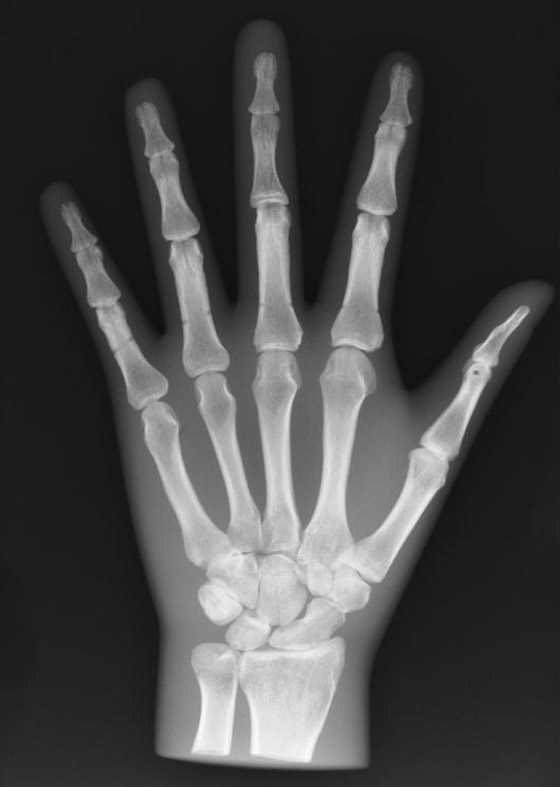

5- اكتشاف الأشعة السينية (X-Rays): استطاع العالم الألماني (ويليام كونراد رونتجن Wilhem Conrad Rontgen )اكتشاف الأشعة السينية(X-Rays) أحد أعظم الاكتشافات العلمية في العام 1895 للميلاد حيث كان يعمل في جامعة (فورتسبورك)، وحاز على هذا الاكتشاف جائزة نوبل للفيزياء عام 1901، وكان قد ولد في شهر آذار من العام 1845 وتوفي في العاشر من شهر شباط عام 1923 للميلاد.